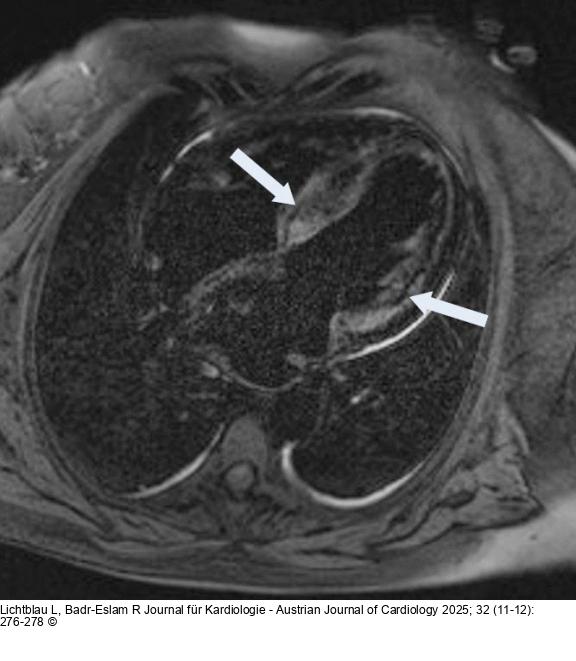

Abbildung 1: MRT MR des Herzens, 4-Kammer-Blick: LGE-Anreicherung im Bereich des Septums und LV (Pfeil) |

Abbildung 1: MRT

MR des Herzens, 4-Kammer-Blick: LGE-Anreicherung im Bereich des Septums und LV (Pfeil) |